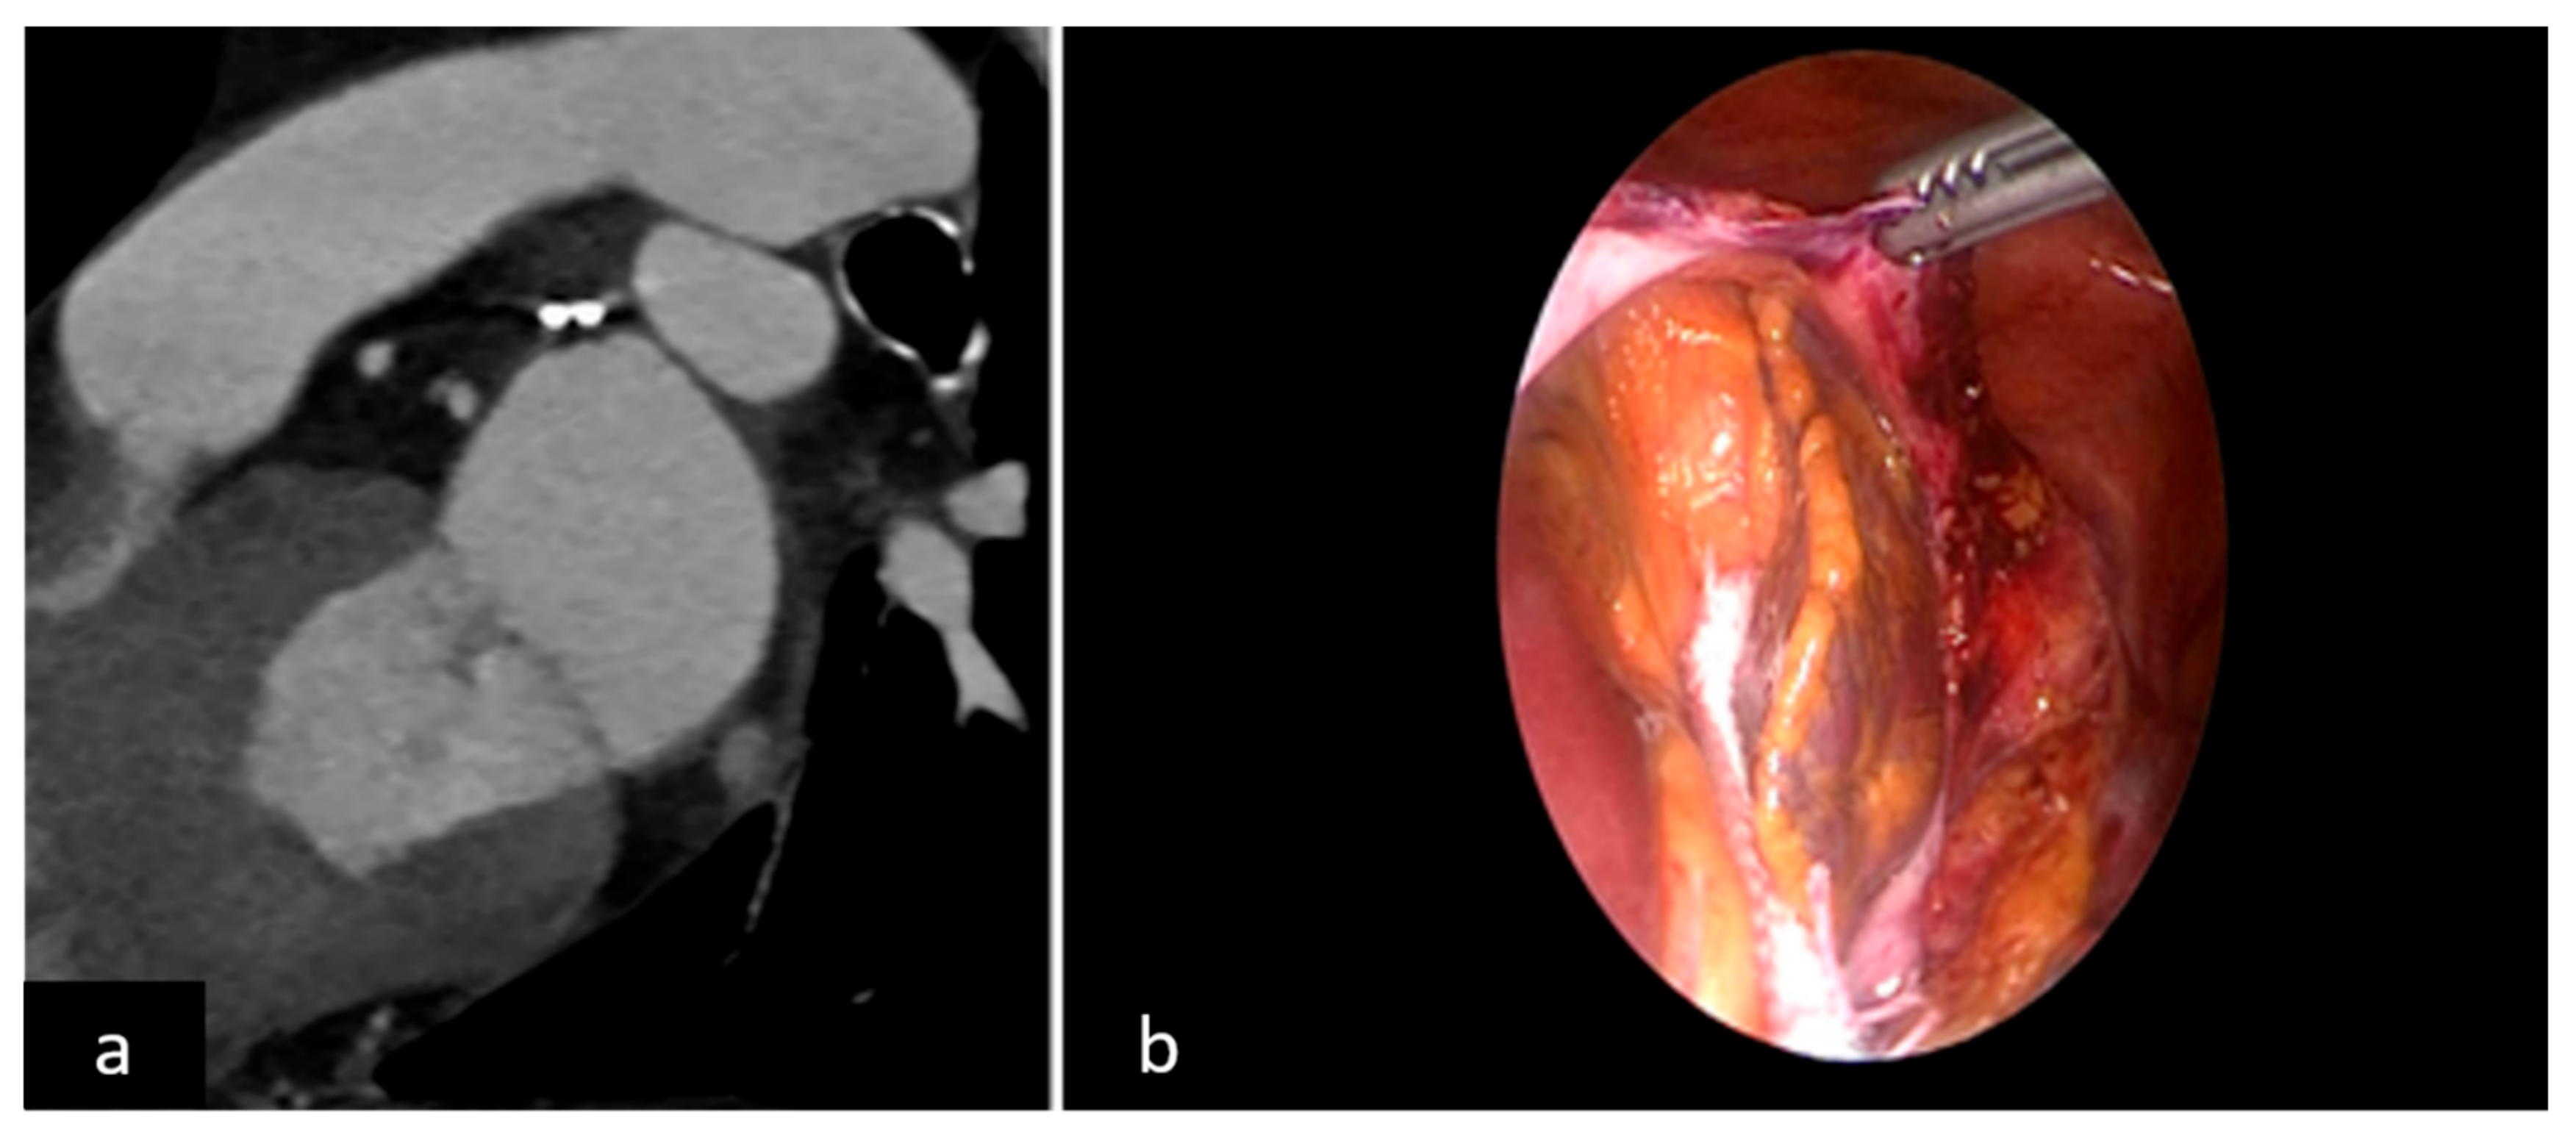

2.2. LAAO-T Procedure

2.3. LAAO-P Procedure

2.4. LAAO-T and LAAO-P Procedures: Role of Echo Imaging